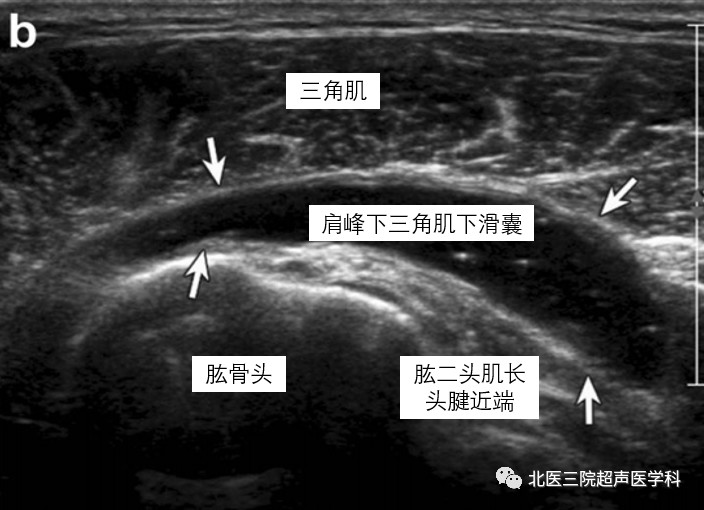

病例2--82岁老年女性,SASD内积液。超声显示肱二头肌长头腱近端浅方SASD内大量无回声(白箭)。